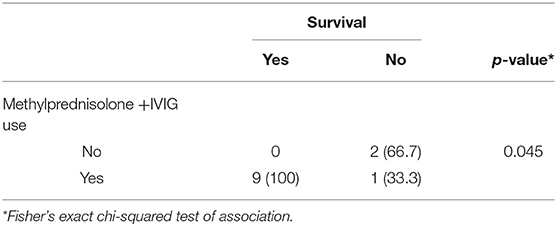

Table 4 summarizes the treatment received. Outcomes were variable among our cases. Five patients had improvements in motor and cognitive functions; two patients had dystonia, two patients had speech delay, and early death in three patients (25%). Nine of the 12 patients had survived; all those survivors had received a combination of IVIG and IV methylprednisolone. Two patients who did not receive this combination of therapy died. However, statistical significance cannot be established due to singularity of the measured variables due to the small sample size. Table 5 shows prognoses and final outcomes. Survival was associated significantly with the use of IVIG and IV methylprednisolone combination (P = 0.043, Fisher's exact chi-squared test), demonstrated in Table 6.

Table 6. The Bivariate association between IVIG and IV methylprednisolone use with the survival: (n = 10).

The treatment of ANEC is not well-established and remains controversial. A previous study found that early intervention within 24 h of the presentation by IV Methylprednisolone 30 mg/kg/day for 5 days or dexamethasone 0.6 mg/kg/day divided into two to four doses for 2–4 days was associated with a good prognosis, while patients treated after 24 h had poorer outcomes. In the same study, patients who had brainstem lesions did not show significant recovery. On the other hand, IVIG administration was not shown to have significant prognostic value (24). Despite the prognostic value of administering IV Methylprednisolone within 24 h of presentation, the treatment of ANEC remains challenging as physicians hesitate to start their patients on IV Methylprednisolone early, since the condition may mimic herpetic encephalitis. The presence of characteristic neuroradiological features and initial negative CSF study may encourage treating physicians to consider the initiation of steroids early in the course of the disease. Nine of the patients in our study who received IV Methylprednisolone and IVIG had acceptable outcomes in motor and mental functions during their follow up. However, there were no standardized outcome measurements done for the patients. Survival was associated significantly with the use of IVIG and IV methylprednisolone combination. It is difficult to judge the efficacy of PLEX based on two patients. The prognosis of ANEC is generally variable; however, multiple studies have shown improvement over time (15). It is assumed that patients under 2 years old with increased liver enzyme levels and brainstem lesions have a poorer prognosis (9, 25–28). Liver function tests did not help determine vital prognosis. Liver enzyme levels were mildly to moderately increased in patients who died, while one case had a better prognosis despite the significantly higher aminotransferase levels. Brain edema and brainstem involvement, documented in five of our patients, led to variable outcomes, while the degree of severity of brainstem involvement may play an important role in determining prognosis.